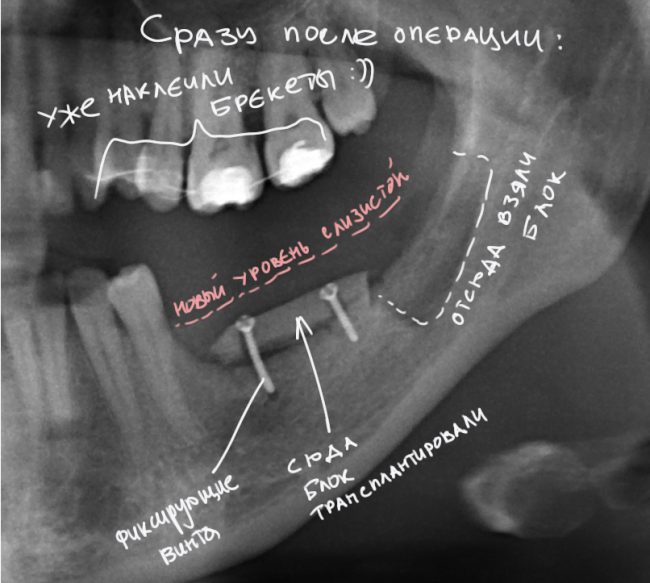

Вот снимок после операции:

сразу после остеопластики

И с обозначениями:

1

«Пустое пространство» под блоком мы заполнили аутокостной стружкой, а сверху закрыли барьерной мембраной BioGide. Самое сложное в данной работе было, на мой взгляд, подогнать размер блока, «собрать» слизистую оболочку и наложить швы так, чтобы пациентка не кусала послеоперационную рану верхними зубами. Кстати, как видите, на верхние зубы уже наклеили брекеты — начали ортодонтическое лечение.

На верхней челюсти — микровинты в качестве кортикальной опоры, необходимой для интрузии зубов. Поскольку костная ткань верхней челюсти не очень плотная, и винты, как оказалось, не дают нужной поддержки, в дальнейшем планируем заменить их на микропластину.